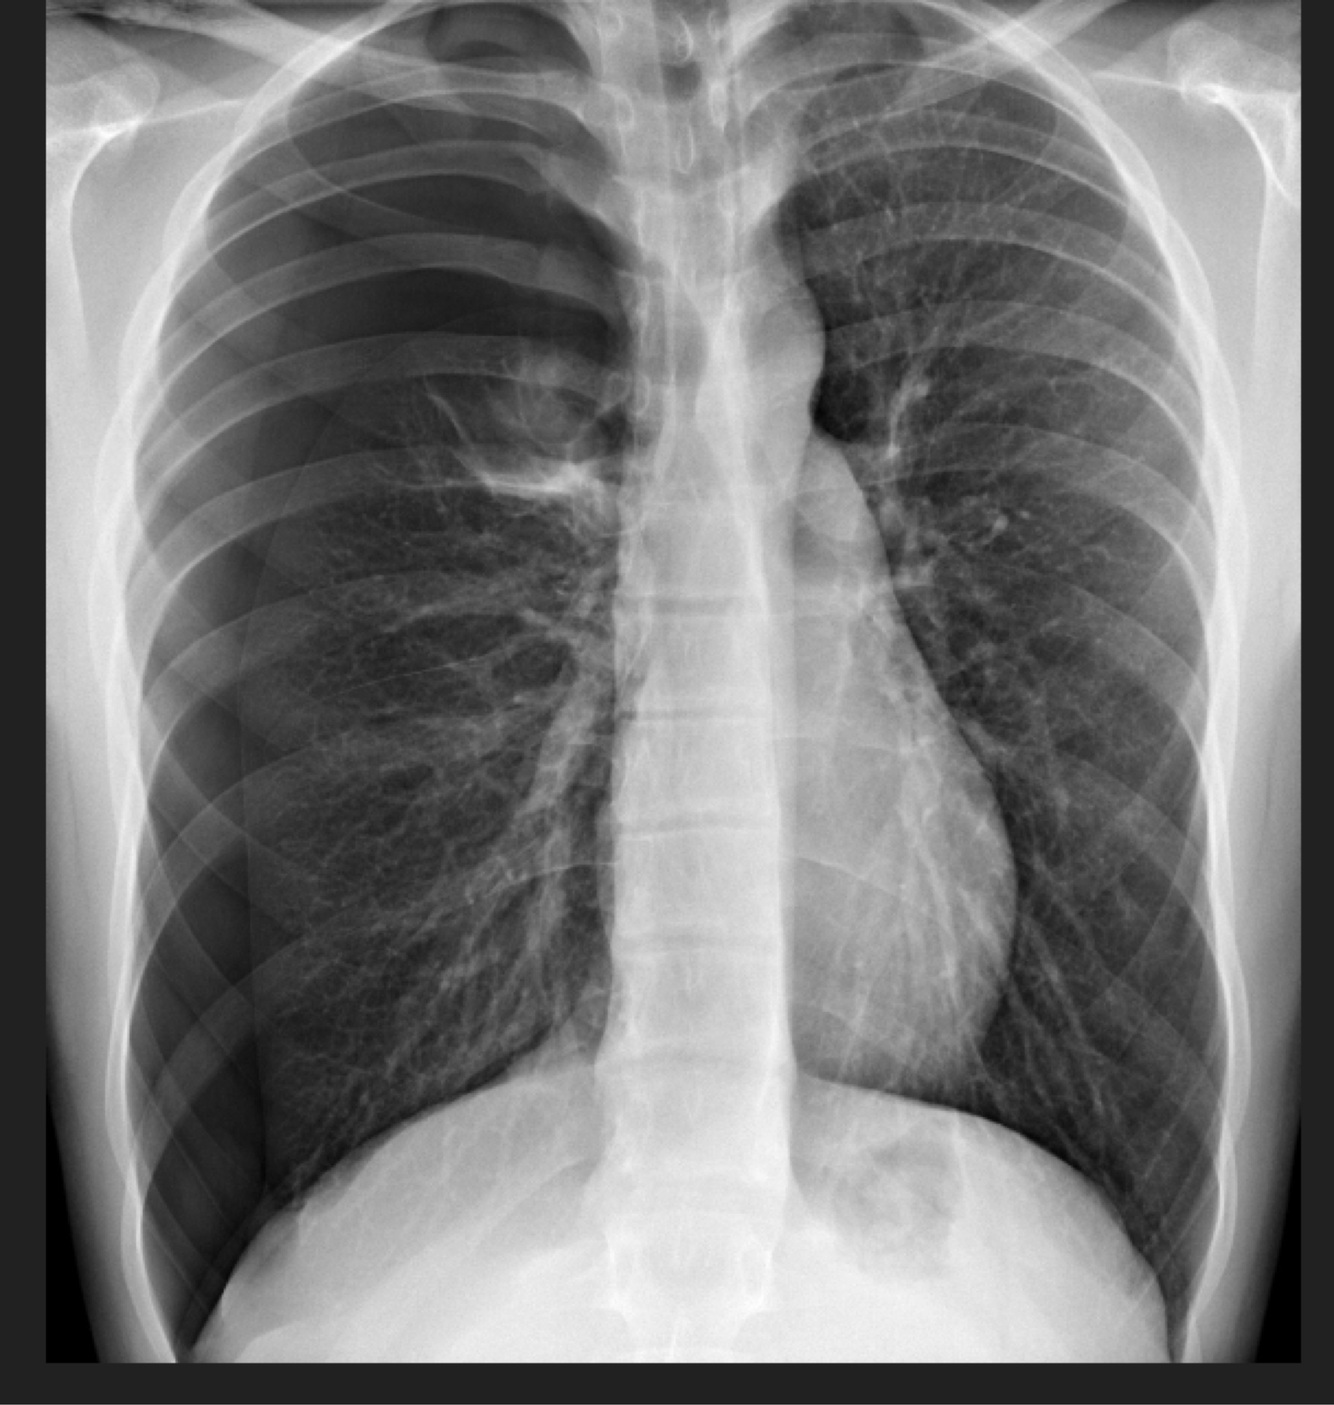

6

Q

Femenino de 82 años, el dato extrapulmonar aparente es:

A

Neurofibromatosis